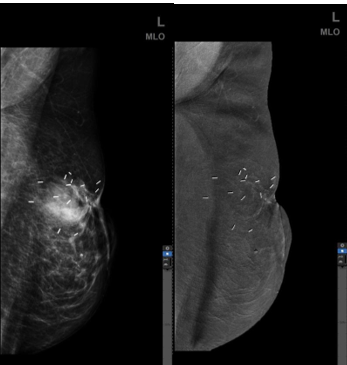

病例二

(左图)传统数字乳腺X线摄影(FFDM),左乳保乳术后,传统2D图像显示左乳上象限术区结构纠集、扭曲。

(右图)乳腺高清对比增强技术(CESM HD),对比增强后该区域未见明显异常强化,提示术后改变。